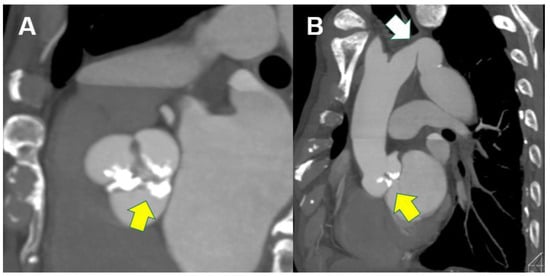

3.4. Utility of the Evaluation of Congenital Abnormalities on Computed Tomography

- Egbe, A.C.; Borlaug, B.A.; Miranda, W.R.; Karnakoti, S.; Ali, A.E.; Younis, A.; Connolly, H.M. Sex Differences in Outcomes of Adults with Repaired Coarctation of Aorta and Concomitant Aortic Valve Disease. CJC Open 2024, 6, 1386–1394. [Google Scholar] [CrossRef]